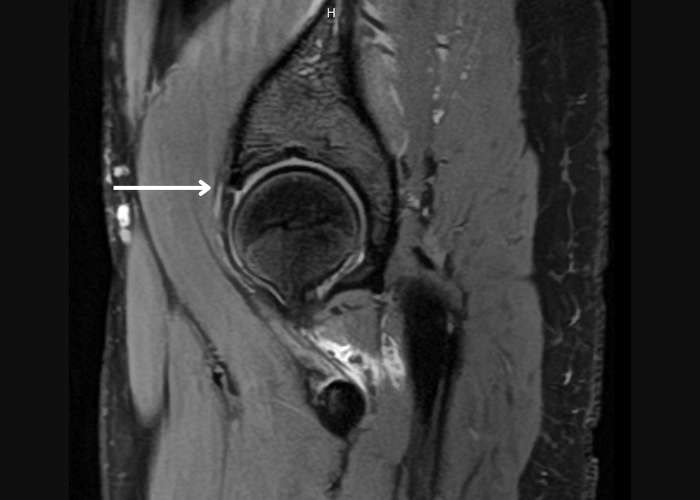

- MRI or MR arthrogram to visualise the labrum and detect tears